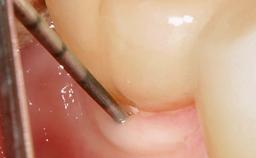

Reconstructive Treatment of a Peri-Implantitis Defect at an Implant in a Mandibular Molar Site

In this case, Mario Roccuzzo utilizes surgical bone regeneration treatment around implant 46 using a bone graft substitute and a connective tissue graft to resolve peri-implant inflammation, reduce the probing depths, and prevent further progression of disease.

A 58-year-old-male patient was referred in February 2007 for implant placement in the right mandibular molar area. Two tissue level implants were inserted at sites 44 and 46, respectively, to support a three-unit fixed dental prosthesis (FDP).